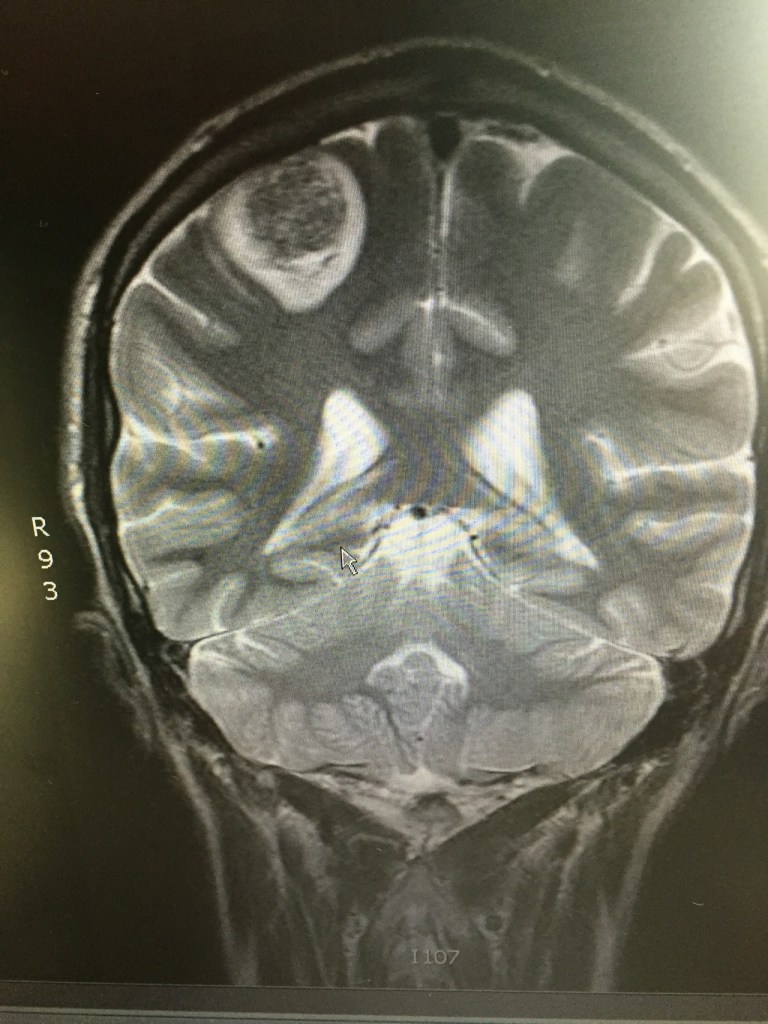

The following day, while driving back from an appointment, I lost complete mobility in my left arm. Unsure if this was a seizure, a stroke…, or a clotting issue, my sister took me to the ER. As most of my ER stories go, they did several tests, the first of which, after vitals, was a head CT scan. What they discovered explained the loss of mobility/motor function in my left arm – a 3.2cm lesion on the back rear (right) lobe in and around the parietal and occipital lobe. (this is what I’m piecing together from the various doctors I’ve met. still trying to grasp the facts.) My MRI on Jan 30 showed no sign of this (what is assumed to be) metastatic spread. Unlike the other brain lesion that was dealt with using solely stereotactic radiosurgery (SRS) in early October (2016), this one will initially be surgically resectioned, and then SRS will be used. The main reason for that is its size.

This will most likely push back the stem cell transplant a few weeks or so, considering the healing time and then the radiation therapy afterward. That & this new and particularly aggressive/fast-growing brain met seem most urgent.

The surgical resection is scheduled for tomorrow, Apr 30, 2017.